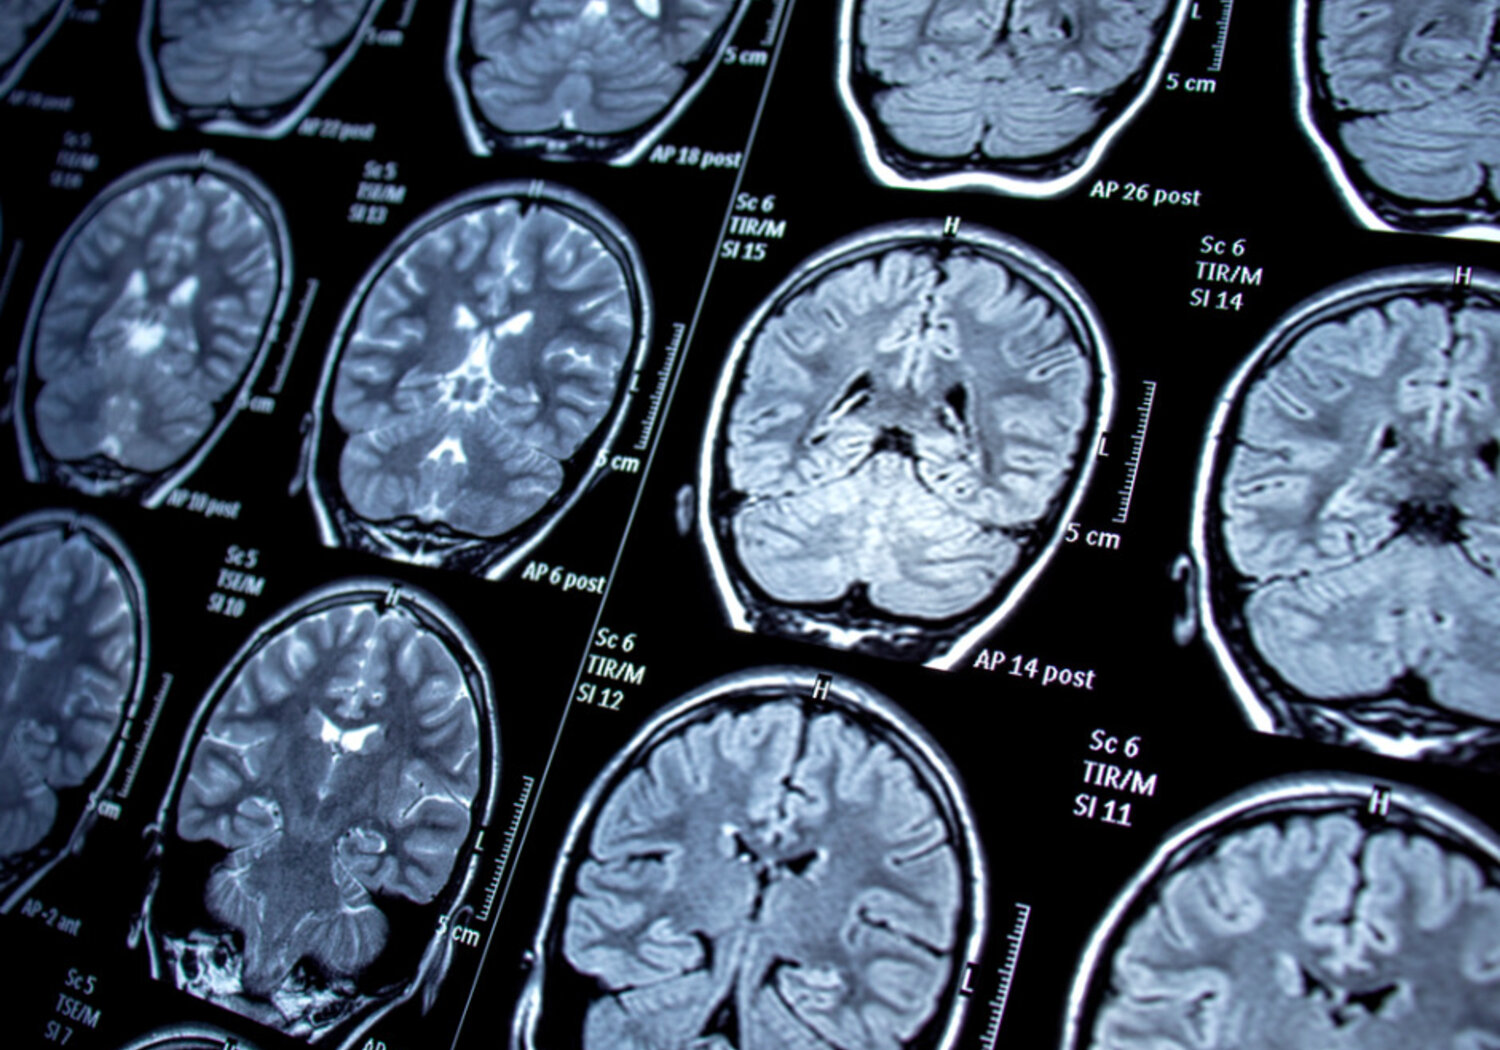

Magnetic resonance imaging (MRI) uses radio waves and large magnetic fields to help identify conditions ranging from damaged ligaments to cancer. Around 40 million MRI scans are performed each year in the EU, but the size and cost of scanners means that not all European citizens have equal access to this form of medical diagnosis.

‘Low-field MRI’ is a portable form of the standard MRI scanner, opening opportunities to provide treatment at a patient’s locality. However, these machines currently lack metrological traceability on the results they give. These instruments also lack the accredited documentation blueprints of hardware and software required by the EU’s Medical Device Regulation (EU)2017/745 (MDR).